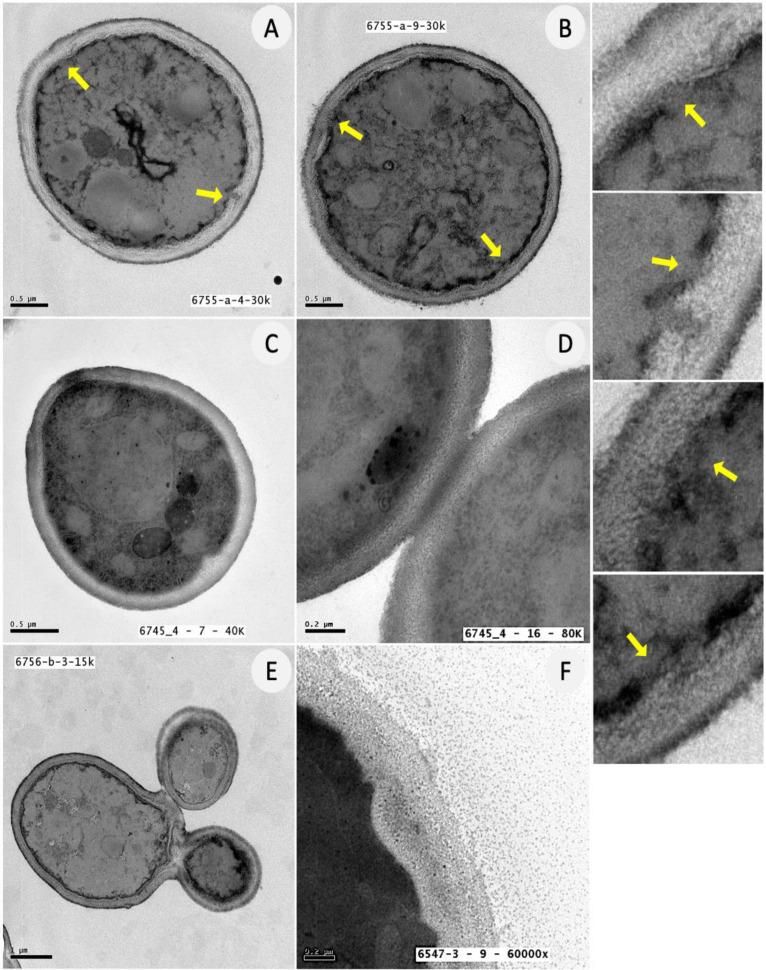

ATRA completely inhibited the fungal growth, by acting as both fungicidal (at 300 µg/mL) and fungistatic (at 150 µg/mL) agent. Furthermore, ATRA was found to negatively affect biofilm formation in terms of biomass, metabolic activity and morphology, in a dose-dependent manner, and intriguingly, its efficacy was as that of amphotericin B (AmB) (2-0.12 μg/mL). Additionally, transmission electron microscopy (TEM) analysis showed that at 300 μg/mL ATRA induced plasma membrane damage in cells, confirming its direct toxic effect against the fungus.

ATRA通过作为杀菌剂(300μg/mL时)和抑菌剂(150μg/mL时)完全抑制真菌生长。此外,发现ATRA在生物量、代谢活性和形态方面以剂量依赖的方式对生物膜形成产生负面影响,有趣的是,其效果与两性霉素B(AmB)(2 - 0.12μg/mL)相当。此外,透射电子显微镜(TEM)分析表明,在300μg/mL时,ATRA诱导细胞中的质膜损伤,证实了其对真菌的直接毒性作用。